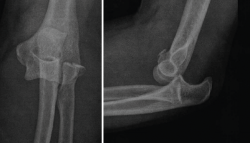

3. Radiografías simples de codo en proyección anteroposterior (AP) y lateral (Figura 5).

Figura 5. Radiografías simples de codo en proyección anteroposterior y lateral. En estas radiografías puede apreciarse una luxación posterolateral de un codo izquierdo, además de fractura de la cabeza del radio y fractura de la punta de la coronoides.